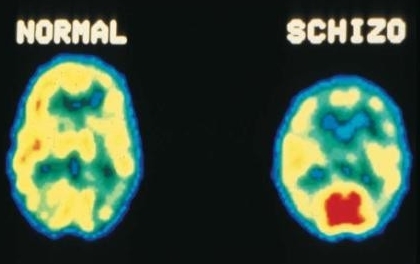

ESQUIZOFRENIA

Um surto psicótico com delírios e alucinações que distorcem a realidade e a pessoa esquizofrênica é mal compreendida e apontada como “louca”. É assim que vivem mais de 1% da população mundial. No país são 1,6 milhões de brasileiros que convivem com essa doença. A esquizofrenia é um transtorno mental crônica na qual realidade e […]